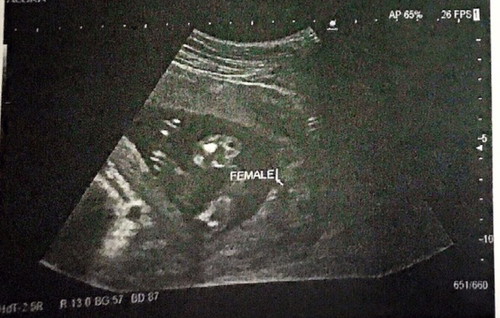

แม่ๆช่วยดูหน่อยค่า น้องเป็น ผญ ชัดเจนใช่ไหมคะ 18w4d

คุณพ่ออยากได้ลูกชายมาก จากภาพอันตร้าซาวน์หมดสิทธิ์ลุ้นชายแล้วใช่ไหมคะ หวังว่าช้างน้อยจะงอกคงหมดสิทธิ์แล้วใช่ไหมคะ ??❤️

เราก็อยากได้ผู้ชายค่ะ ตอน 16 วีคหมอก็บอกว่าผู้หญิง 80% แล้ว เพราะยังเล็กอยู่มากและน้องหนีบไว้นิดนึงมีสิทธิ์จะเป็นผู้ชายก็ได้ แต่ที่ดูคือไม่มีติ่งยื่นออกมาเลย จนตอนนี้ 34 วีคแล้วค่ะ ซาวด์มาหลายรอบก็ไม่มีติ่งออกมา ผู้หญิงแน่นอนแล้ว

ดูจากภาพซาวน์บอกว่าหญิงชัดเจนค่ะแม่ บ้านนี้อยากได้ลูกสาวมากกกก ซาวน์มาแหลมมาเลยค่ะ ผลน้ำคร่ำก็บอกว่าชาย หมดสิทธิ์ลุ้นเหมือนกันค่ะ แต่ไม่แน่นะคะของแม่ เคยมีคนรู้จักช่วง18-19สัปดาห์ผลซาวน์เป็นผู้หญิง แต่พออายุครรภ์เยอะๆซาวน์ใหม่เป็นผู้ชาย